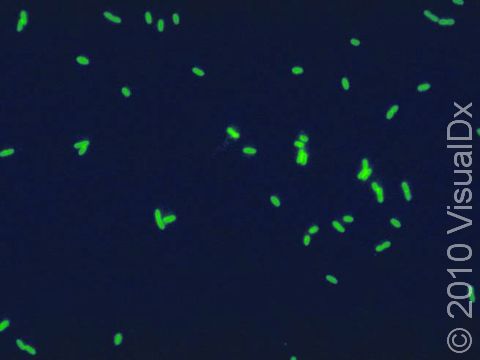

Legionellosis is the name for infection caused by the Legionella pneumophila bacterium. Infection can take two forms: the more serious legionnaires’ disease, which is a pneumonia, and the less serious Pontiac fever. The L. pneumophila bacterium got its name from an outbreak at a convention of the American Legion in 1976, when many people staying in the same hotel developed an unusual pneumonia. L. pneumophila is found naturally in water and is often found in the water systems of large buildings, such as the heating and cooling elements of hotels and hospitals.